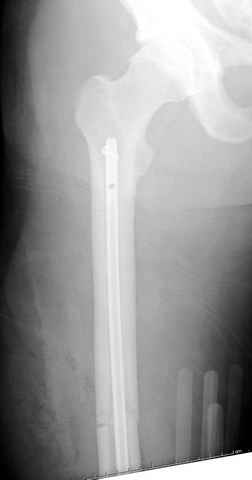

03.14.2005

больному 42, автоавария, политравма, открытая черепномозговая травма, безсознании, открытый перелом бедра, размозжение мягких тканей, дефект кожи на передней поверхности бедра около 13 см2 от ожога, компартмент синдром.

По поводу открытого перелома больной ургентно взят на ретроградное интрамедулярное штифтование, после рутинного дебрайдмента и фасциотомии на бедре и на голени.

перелом бедра

интраоперационные